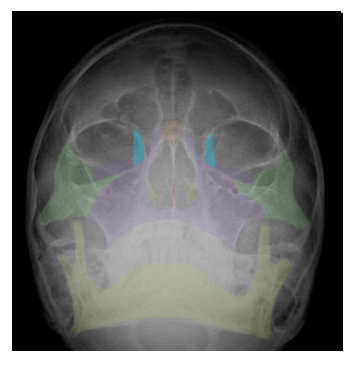

| LACRIMAL |

| INFERIOR NASAL CONCHA |